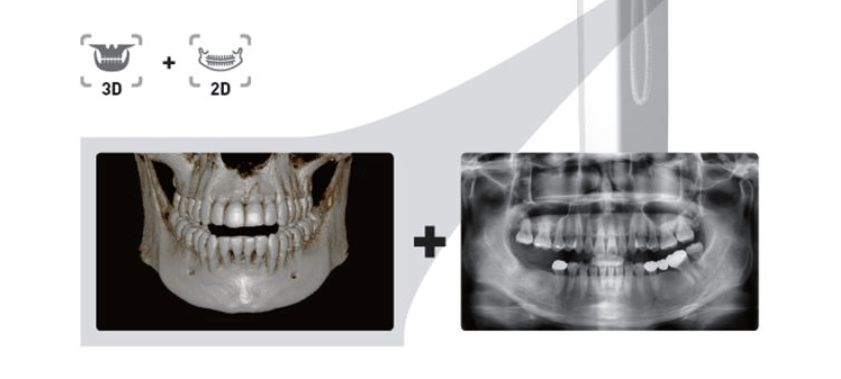

- ONE SCAN TWO IMAGES : สำหรับคนไข้ที่ถ่าย CT และต้องการภาพ PANO ด้วยคุณสมบัติของ Software ทำให้สามารถสร้างภาพ PANO ได้หลังจากที่ถ่าย CT โดยที่ไม่ต้องถ่ายภาพ x-ray ใหม่ ประหยัดค่าใช้จ่ายคนไข้ และทำให้คนไข้ปลอดภัยโดยไม่จำเป็นต้องรับปริมาณรังสีเพิ่มจากการถ่าย x-ray ซ้ำ